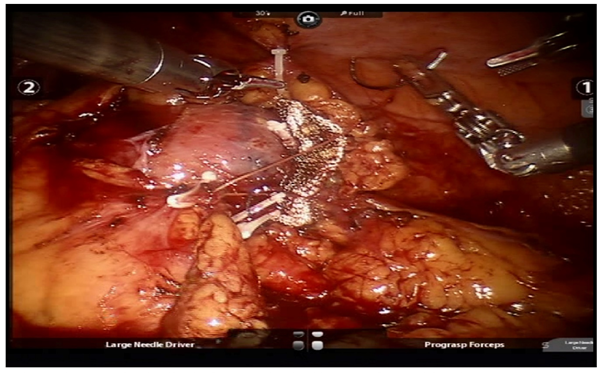

All patients underwent pre-operative contrast-enhanced computed tomography (CECT) of abdomen with renal angiography for tumour and vascular anatomy with 3D reconstruction (Figure 1). Routinely ipsilateral ureteric catheter was placed after anaesthesia. Surgical steps that were sequentially followed in all cases included ipsilateral colonic mobilization along with identification of ureter, gonadal vessels and psoas muscle; identification and mobilization of the renal artery and vein; mobilisation of the upper pole according to the need; demarcation of the tumour boundary with the help of intraoperative ultrasound; hilar clamping (renal artery and vein separately clamped); resection of the tumour; two layered renorrhaphy (Figure 2) with barbed suture with application of haemostatic agents (Gelatin granules with human thrombin and oxidised regenerated cellulose) and peri-renal drain placement. Zero-ischemia RPN were performed premeditatedly for cases with small (<4cm) cortical renal mass (predominantly exophytic) in favourable positions (lateral, lower and upper pole) and where single isolated feeder vessel was well identified (Figure 3). Ipsilateral ureteric catheter was removed routinely on 2nd post-operative day. We replaced the ureteric catheter with double-J stent where pelvicalyceal system were opened intraoperatively or tumour was larger one in vicinity to the pelvicalyceal system.

Figure 1(a) Computed Tomography with renal angiography showing left lower pole renal mass; (b) 3D reconstruction

Figure 2 Renorrhaphy (barbed suture fixed with weck clips, oxidized regenerated cellulose mesh put at the raw site).

Figure 3 (a) right upper pole renal mass selected for zero ischemia (b) 3D reconstruction.